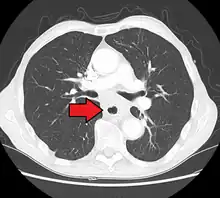

If the cancer has spread elsewhere, symptoms related to metastatic disease may appear. Common sites of spread include nearby lymph nodes, the liver, lungs and bone.[14] Liver metastasis can cause jaundice and abdominal swelling (ascites). Lung metastasis can cause, among other symptoms, impaired breathing due to excess fluid around the lungs (pleural effusion), and dyspnea (the feelings often associated with impaired breathing).

Additional testing is needed to assess how much the cancer has spread (see § Staging, below). Computed tomography (CT) of the chest, abdomen and pelvis can evaluate whether the cancer has spread to adjacent tissues or distant organs (especially liver and lymph nodes). The sensitivity of a CT scan is limited by its ability to detect masses (e.g. enlarged lymph nodes or involved organs) generally larger than 1 cm.[43][44] Positron emission tomography is also used to estimate the extent of the disease and is regarded as more precise than CT alone.[45] PET/MR as a novel modality has shown promising results in preoperative staging with fair feasibility and good correlation in comparison to PET/CT. It can enhance tissue differentiation with lowering the radiation dose to the patient.[46] Esophageal endoscopic ultrasound can provide staging information regarding the level of tumor invasion, and possible spread to regional lymph nodes.